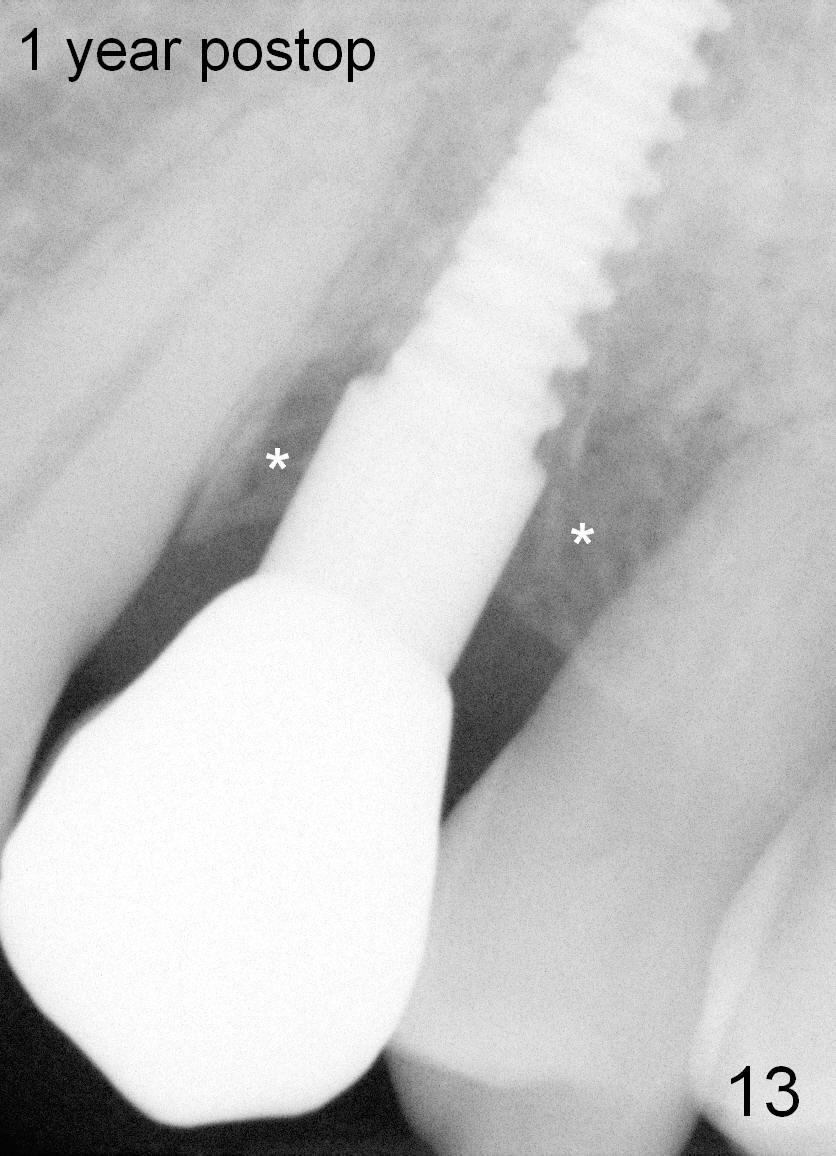

Crestal bone grows 2 months (Fig.11), 3 months (Fig.12), 1 year (Fig.13) and 2 years 3 months (Fig.14) postop. When the periodontally-affected tooth is removed and bone graft is placed around the most coronal thread of the implant, bone will regrow as time passes by.